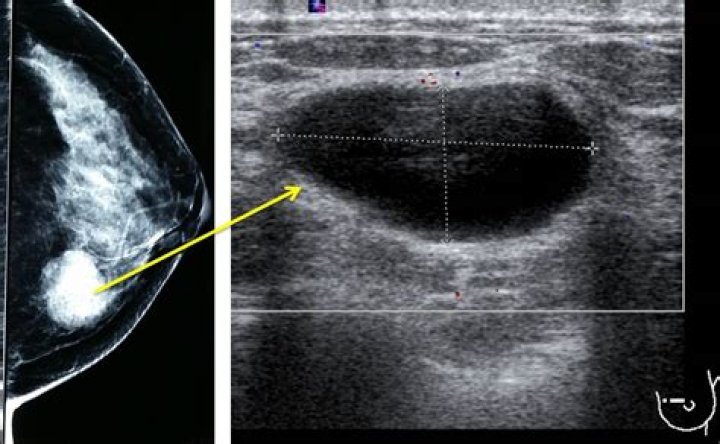

Where are breast cysts usually located?

Where are breast cysts usually located? Breast cysts may be found in one or both breasts. Signs and symptoms of a breast cyst include: A smooth, easily mo...